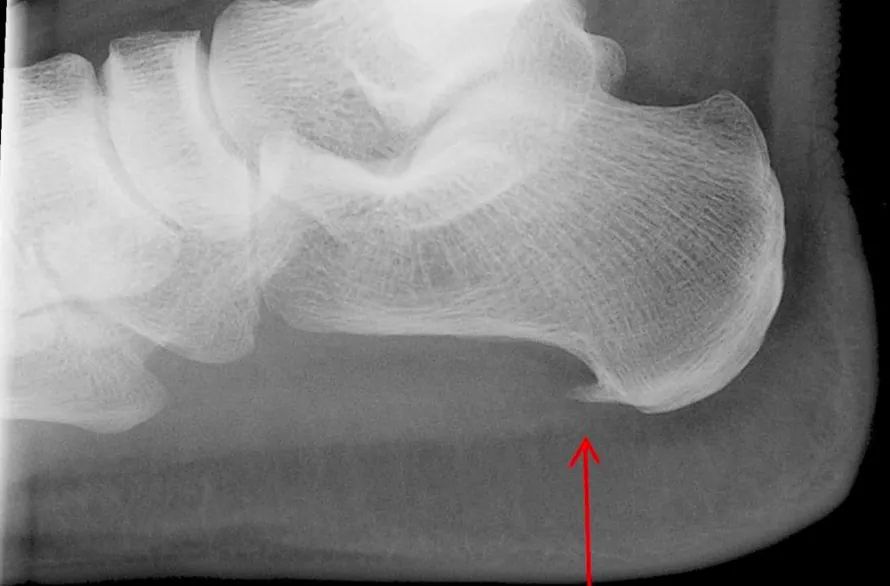

Es un crecimiento del hueso del talón en forma triangular o de lanza.

Si presentas estos síntomas visita a tu médico. El diagnóstico se realiza mediante la visualización del espolón en una radiografía.